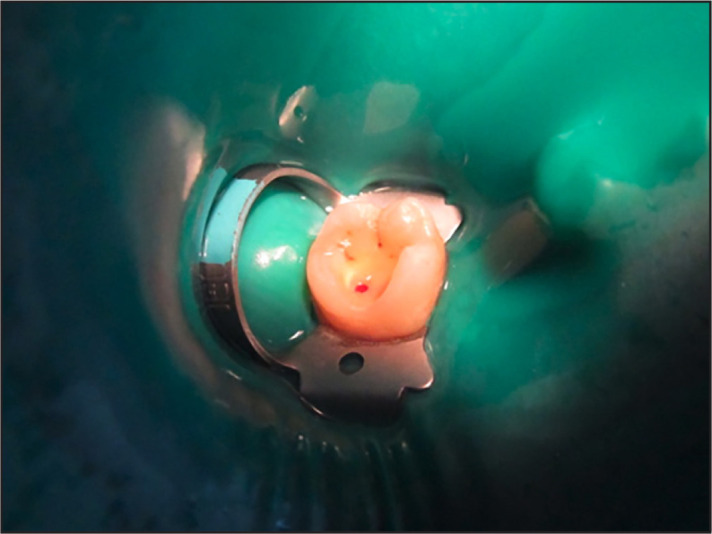

Methods: One hundred and fifty patients diagnosed with reversible pulpitis with deep carious lesions were included in this study. Patients were randomly allocated into three groups (n=50), Group C: CEM group, Group M: MTA group, and Group D: CH (Dycal) group. After caries removal by mechanical excavation except for one carious spot, the removal of which resulted in the exposure of the pulp, the final carious spot was removed with a sterile no.2 round carbide bur. After haemostasis, the pulpal wound was dressed by a capping agent, followed immediately by permanent restoration. Patients were assessed for successful outcomes based on positive vitality tests, absence of clinical signs and symptoms, and PAI scores after 1, 3, 6, 12, and 18-month follow-up periods. The ANOVA test was employed to analyse quantitative variables, and the Pearson Chi-square test was used for qualitative variables. A Bonferroni Test was employed as the post hoc test for intergroup comparison. The significance level was set at p≤0.05 within all tests.

Abstract Image